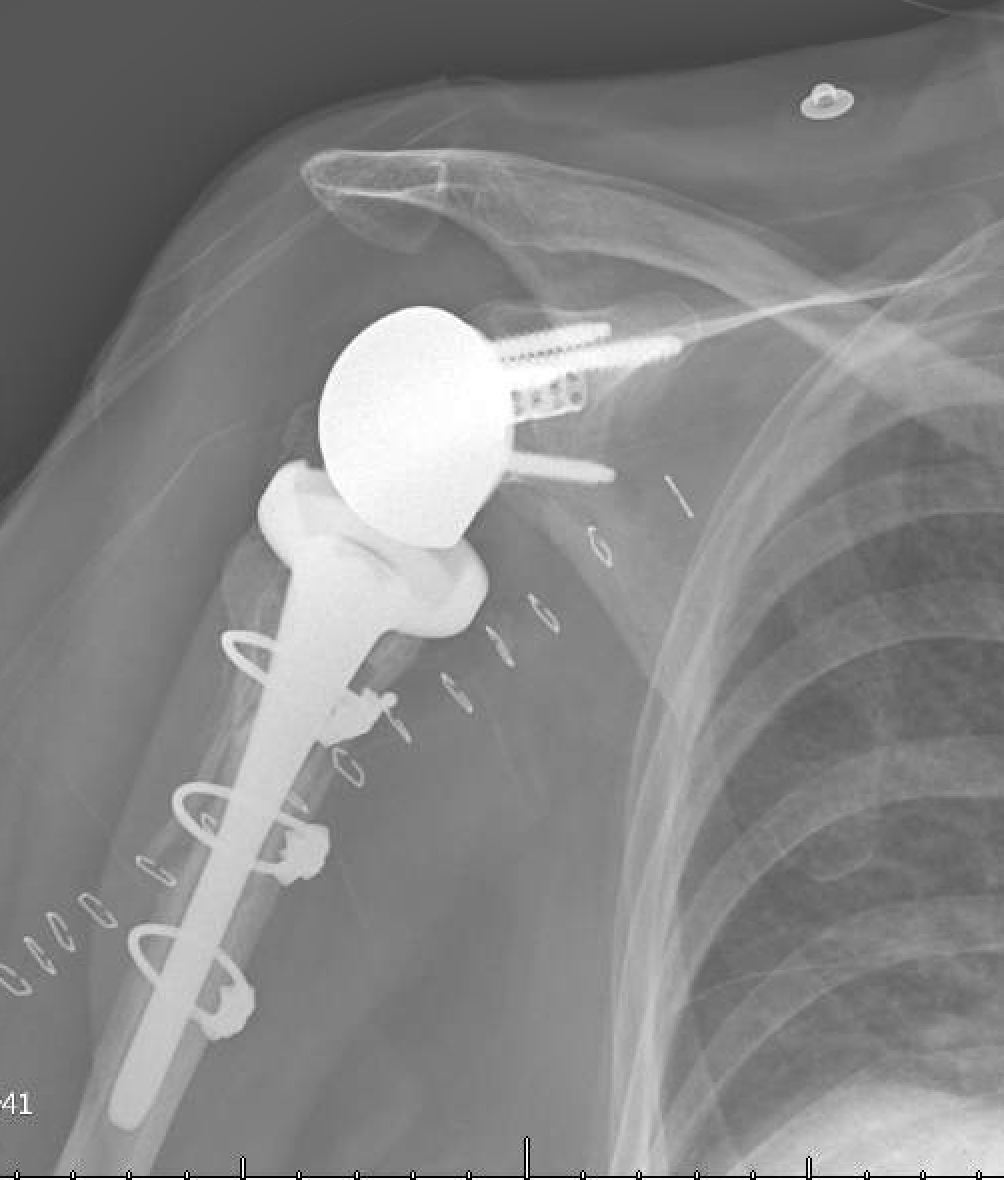

What Happens If Shoulder Replacement Fails . If the artificial shoulder joint wears out or otherwise fails, a surgeon may recommend a. Dislocation, infection, implant loosening from bone, and dissociation. The incidence of failure after shoulder arthroplasty is lower than other major joint reconstructions. When it occurs after surgery to repair a shoulder injury, then it’s considered a failed shoulder stabilization surgery. The most common modes of failure for reverse shoulder replacements are: Reverse total shoulder arthroplasty (rtsa) is a terrific new tool, but failures invariably occur due to infection, instability, baseplate. Revision surgery for shoulder replacement. Revision surgery for total shoulder replacement. If the artificial shoulder joint wears out or otherwise fails, a surgeon may recommend a revision surgery. The results of shoulder joint replacement are often excellent, but failure of shoulder arthroplasty can result because of persistent pain, stiffness, infection, component.

The most common modes of failure for reverse shoulder replacements are: When it occurs after surgery to repair a shoulder injury, then it’s considered a failed shoulder stabilization surgery. If the artificial shoulder joint wears out or otherwise fails, a surgeon may recommend a revision surgery. The results of shoulder joint replacement are often excellent, but failure of shoulder arthroplasty can result because of persistent pain, stiffness, infection, component. Reverse total shoulder arthroplasty (rtsa) is a terrific new tool, but failures invariably occur due to infection, instability, baseplate. Dislocation, infection, implant loosening from bone, and dissociation. The incidence of failure after shoulder arthroplasty is lower than other major joint reconstructions. Revision surgery for total shoulder replacement. If the artificial shoulder joint wears out or otherwise fails, a surgeon may recommend a. Revision surgery for shoulder replacement.

What Happens If Shoulder Replacement Fails If the artificial shoulder joint wears out or otherwise fails, a surgeon may recommend a. Reverse total shoulder arthroplasty (rtsa) is a terrific new tool, but failures invariably occur due to infection, instability, baseplate. The incidence of failure after shoulder arthroplasty is lower than other major joint reconstructions. The results of shoulder joint replacement are often excellent, but failure of shoulder arthroplasty can result because of persistent pain, stiffness, infection, component. Dislocation, infection, implant loosening from bone, and dissociation. When it occurs after surgery to repair a shoulder injury, then it’s considered a failed shoulder stabilization surgery. If the artificial shoulder joint wears out or otherwise fails, a surgeon may recommend a. If the artificial shoulder joint wears out or otherwise fails, a surgeon may recommend a revision surgery. Revision surgery for shoulder replacement. Revision surgery for total shoulder replacement. The most common modes of failure for reverse shoulder replacements are: